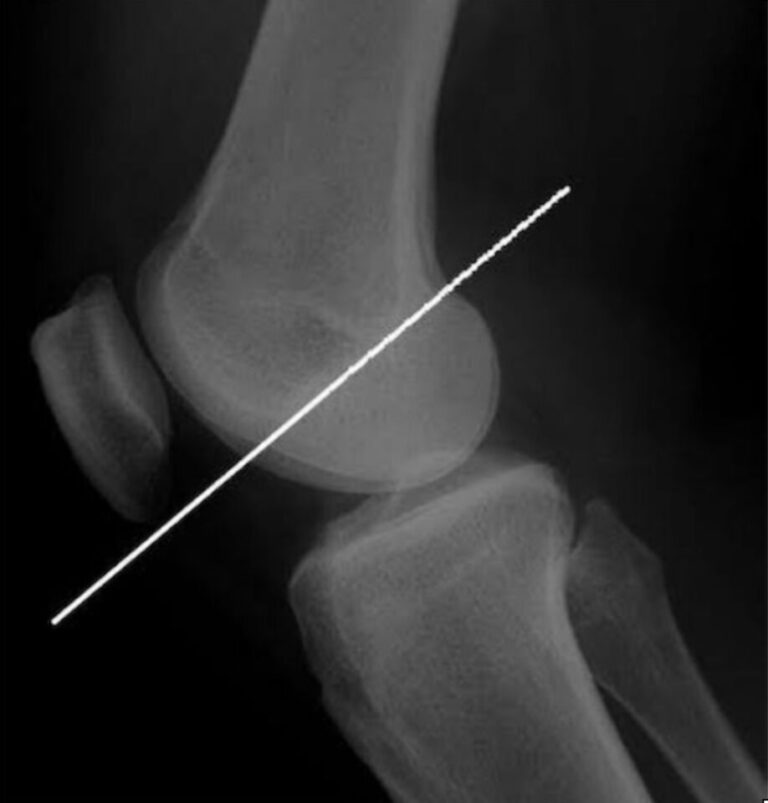

大腿骨顆間部の上縁をなぞるラインです。側面でみるとこのようになります。

顆上骨折のときはこのラインより前から髄内釘を入れるのがコツですね。下から入れてしまうと髄内釘によって伸展変形してしまいます。